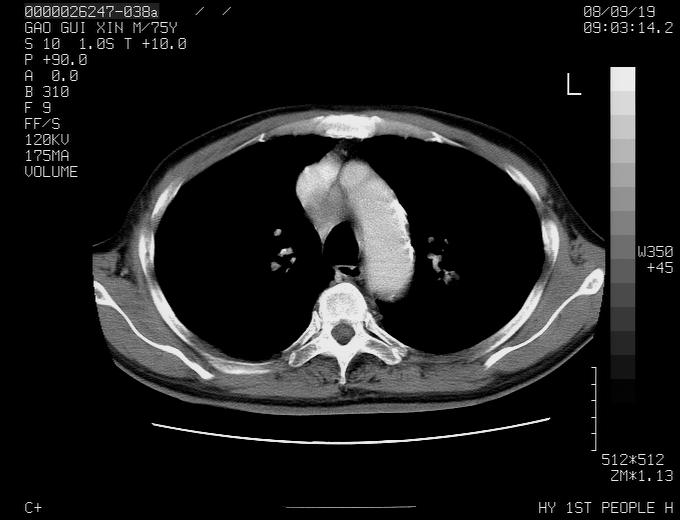

感谢各位老师的意见,左上肺病灶,我本人趋向结核,原因:左上肺见两个类圆形结节,仔细回顾4月份ct似乎原片在该处有条片状密度增高影,强化不明显。

现上传增强片,请各位老师仔细帮我看一下。

右上肺可见条索状影,并可见钙化,左上肺结节可以考虑为结核球,但气管前腔静脉后有肿大淋巴结,本人觉得左上肺结节不能排除转移瘤的可能,右上肺为陈旧性结核灶。

左肺上叶周围性肺癌并纵隔多组lnm.不可能是tb.

左肺上叶尖段瘢痕癌并纵隔淋巴结转移解释更好一些.

1)左肺上叶尖段周围型肺癌并纵隔淋巴结转移。2)冠状动脉及主动脉钙化。